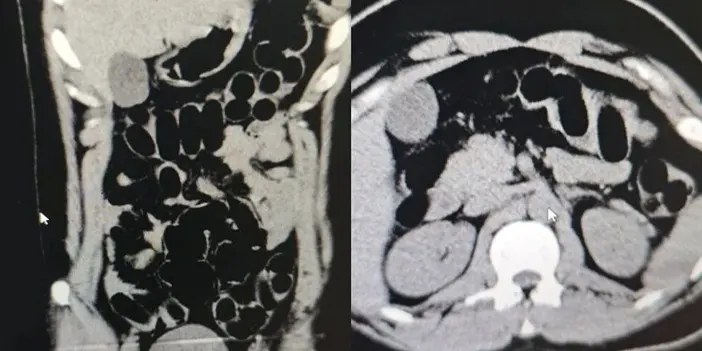

Tomografi Sonucunda Uyuşturucu Tespit Edildi

Hastanede yapılan iç beden muayenesi ve tomografi görüntüleri sonucunda, şüpheli şahsın midesinde uyuşturucu madde taşıdığı belirlendi. Muayene sonrasında şüphelinin midesinden toplam 84 kapsül içerisinde daralı ağırlığı 842 gram olan eroin ele geçirildi.